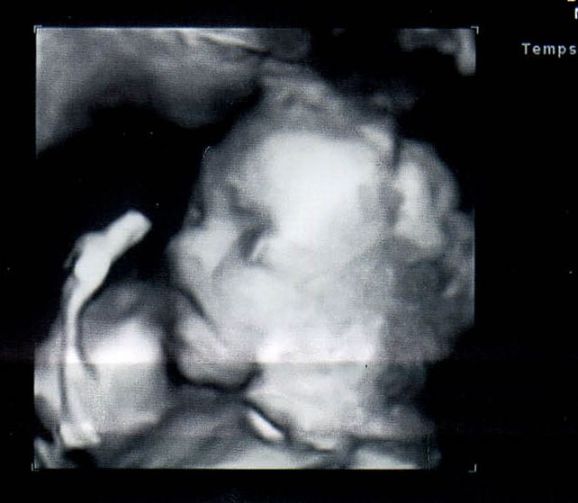

Egyébként Brüsszelből irok, itt dolgozom, az apuka belga. Küldök UH képet a babánkról ami 3 héttel ezelőtt készült.

Andi Kép Dominik

Andee, nagyon édes a kép, gartulálok a fiúcskához!

Andi! Üdv. itt! Nagyon aranyos Dominik! :D Ez a kép olyan, mintha nem is uh-on készült volna, minden vonása szépen látszik.